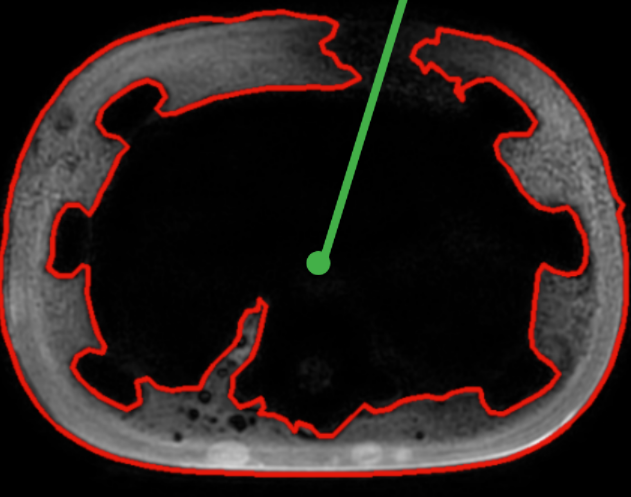

之后还是想着从轴面轮廓开始做,因为其中的操作我明白具体是什么。首先是对原始影像进行预处理,起码得出比较清晰的轮廓。当时想,对于轮廓严重缺失的,直接舍弃,例如下面的轮廓:

对有"轻微凹陷"的轮廓进行修改,像下面这种:

以上是预处理的大致步骤,记得当时寻找轮廓时遇到一个问题,

比如上图,外面的红色轮廓在绿色竖线部分是有缺口的,所以外面的轮廓就不完整,恰好里面绿色轮廓完整,而且和外面”不粘连“,所以扫描出来的结果最大轮廓是里面的轮廓。如下图所示: